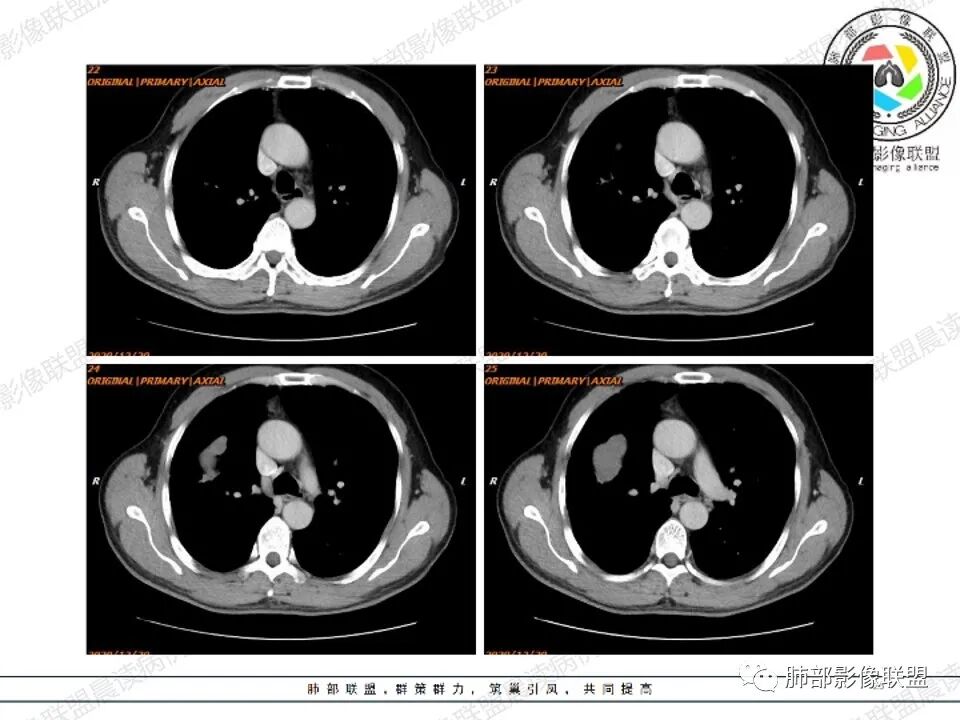

病例二

左肺下叶肿块影平行支气管生长,边缘有纤维索条影,整体边缘平直,略彭隆,边界清楚,伴行支气管堵塞,周围伴有肺气肿,增强扫描强化不明显,无明显实性病变,考虑良性,支气管闭塞?支气管囊肿?平滑肌瘤。

左肺下叶孤立性肿块,形态规则,密度均匀,边界清,周围可以气肿及条索,无强化,左肺下叶后基底段支气管未见发育?考虑发育畸形,支气管囊肿 ?闭锁?先天性囊性腺瘤样畸形?

老年女性,查体发现,左肺下叶不规则实性肿块,边缘平直收缩,无毛刺,周围有纤维牵拉及肺气肿,强化不明显。先天肺发育不良,支气管闭锁。

左肺下叶扁平形结节,边缘光滑平直,边界清晰,周围肺气肿,强化不明显,支持先天肺发育不良,支气管囊肿

左肺下叶不规则高密度早灶,边缘平直为主,界清,周围有肺气肿,无强化,考虑良性病变,支持先天肺发育异常,支气管闭锁,鉴别支气管囊肿,囊腺瘤样畸形。

左肺下叶高密度,边缘光滑,周围肺气肿,强化不明显,ccam?鉴别 隔离

左肺下叶肿块,边缘光滑,支气管动脉伴行,周围肺气肿,考虑支气管闭锁